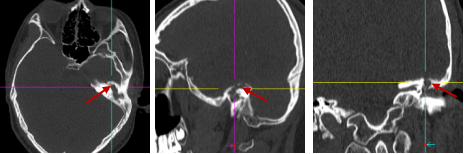

术前 CT(箭头为中耳胆脂瘤骨质破坏缺损处)